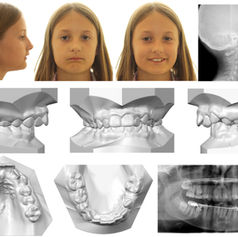

STUDY FINDS MALOCCLUSIONS CONNECTED TO ADHD

A recent study found a connection between children with malocclusion, mouth breathing, and ADHD.

CAFF Team

Mar 1, 20222 min read